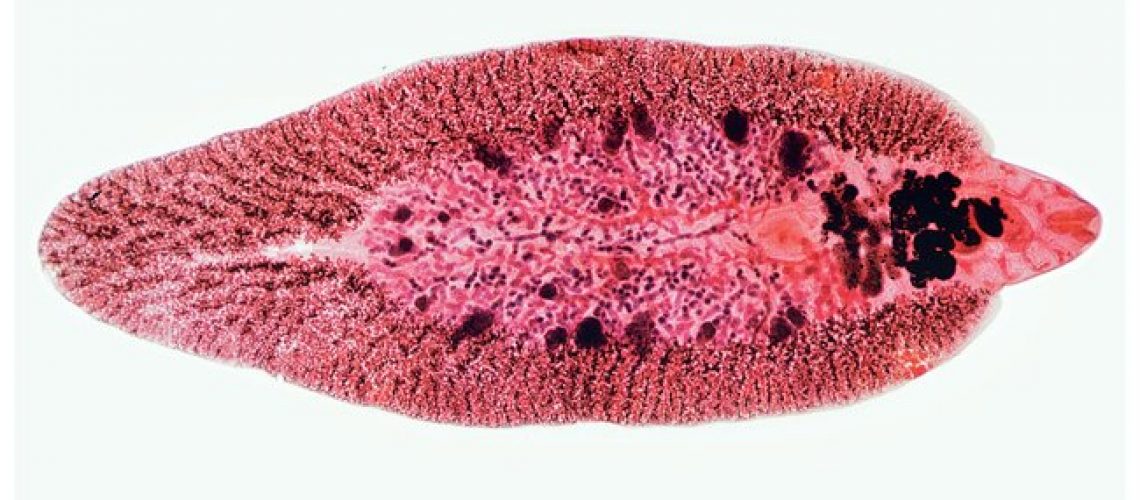

قیمت: 32٬000 تومان - دسته بندی فایل: علوم پزشکیپاورپوینت فاسیولاهپاتیکا

فروش ویژه پاور پوینت حرفه ای فاسیولاهپاتیکا با تخفیف استثنایی فقط 55 هزار تومان تعداد اسلاید: 21 اسلاید